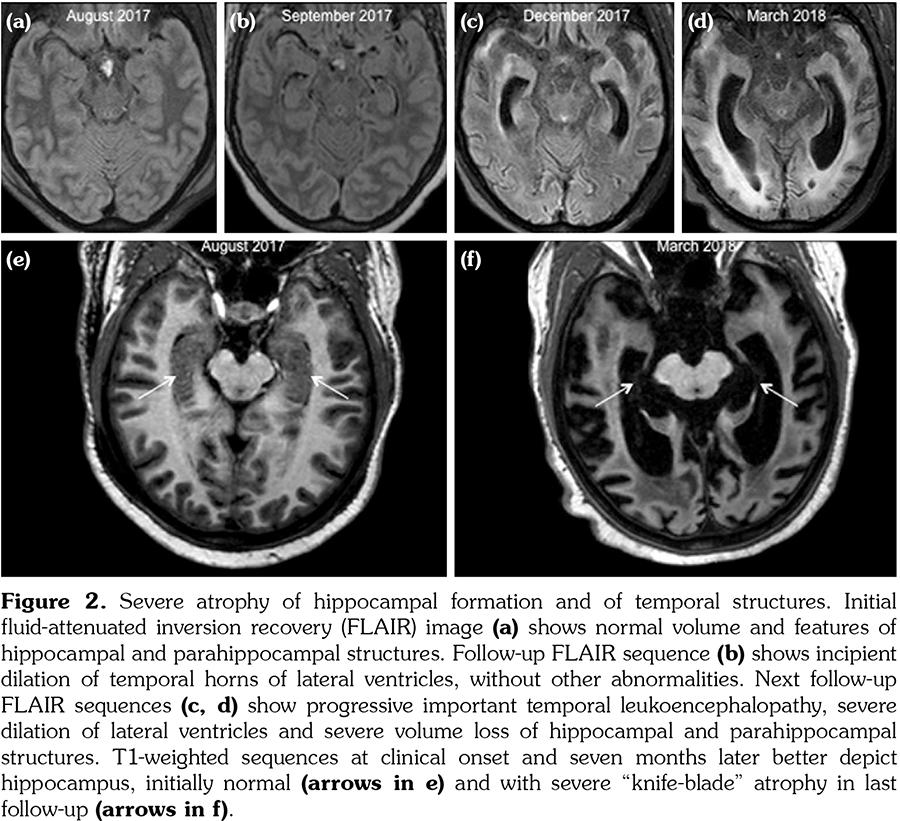

Initial brain MRI, using a standard protocol, was normal (Figures 1a and 2a). Due to rapid deterioration of the neurological status, a follow- up MRI was performed three weeks later (Figures 1b and 2b), including gadolinium administration and angiographic sequences. A mild periventricular nonspecific leukoencephalopathy and an incipient dilation of the supratentorial ventricles were observed. No abnormal contrast- enhancement was present. MRI angiography and venography showed permeability of the vessels. The patient continued to deteriorate, in a span of several weeks, despite initiating high-dose intravenous methylprednisolone. The clinical suspicion of vasculitis was raised and a third MRI was performed, at 3.5 months from the onset, with a specific protocol including vessel-wall three-dimensional (3D)-high-resolution pre- and post-contrast black-blood sequences. This MRI showed severe progression of the leukoencephalopathy, and associated atrophy with marked dilation of the ventricles and the subarachnoid spaces (Figures 1c and 2c). High-resolution vessel-wall sequences showed multiple arterial segments with concentric contrast enhancement of the wall, of proximal and distal distribution (Figure 3), compatible with vasculitis. A treatment with high-dose intravenous cyclophosphamide was started. Clinical follow- up revealed a progressive improvement of the drowsiness with eventually stabilized neurological status, but the cognitive deficit was already extremely impaired. The fourth MRI exam, at seven months from the clinical onset, showed even more severe atrophy (Figures 1d and 2d). A comparative of the hippocampal formation, crucial for the memory circuit, showed normal features on the first MRI (Figure 2e) and marked “knife blade” atrophy on the last study (Figure 2f). Concomitant diseases, including cerebrovascular and cardiovascular events, were ruled out.

Neuropsychiatric SLE remains a major cause of morbidity in patients with SLE, despite all recent diagnostic and therapeutic advances. The most frequent MRI abnormalities in NPSLE are white matter lesions and brain atrophy, although the reported frequencies vary widely, probably reflecting the heterogeneity of the studied population.[7,8] The presence of cortical atrophy was reported at a mean age of 42.5 years in NPSLE.[7] Less frequently, NPSLE patients could present inflammatory lesions on MRI, which usually disappear after aggressive corticosteroid or immunosuppressive treatment. They were reported in 6.5% of patients, and were correlated with low complement levels, supporting an immune-mediated pathogenesis of NPSLE.[9] This pattern has been related to primary cerebral vasculitis, which is however considered to be uncommon in SLE.[2,7,10] Post-mortem histopathological studies reported cerebral vasculitis in less than 10% of NPSLE patients.[9,11] Imaging findings of vasculitis in NPSLE were rarely described, when angiography exams revealed focal beadings and circumferential stenosis of arteries.[12-14] On the other hand, a normal angiography cannot rule out vasculitis, and angiography exams are usually normal if small vessels are involved.[11,14] Despite a low risk of complications, a brain biopsy is usually avoided, lacking of high sensitivity due to the sampling error with high false-negative rates. Therefore, no “gold standard” diagnostic test is accepted to date for the diagnosis of cerebral vasculitis.[13,14] Recently, specific vessel-wall sequences emerged. This type of imaging requires a high-field MRI (3T), and the availability of high-resolution (around 0.5 mm isotropic) 3D-black-blood sequences, acquired pre- and post-gadolinium administration.[14-17] Recent technological advances and guidelines were developed to optimize these sequences and to reduce the acquisition time on the one side,[15] and to provide expert consensus recommendations for their implementation in the current clinical practice on the other side.[16,17] This vessel-wall imaging is increasingly used in other pathologies as aneurysms, dissection and strokes. Prospective comparative studies evaluating the feasibility of 3D-black-blood pre- and post-contrast sequences demonstrated that this technique accurately allows the diagnosis of vasculitis, and the intensity of contrast enhancement of the wall correlated with the mural inflammation.[18] In the last year, several publications including these sequences reported vasculitis of different etiologies as varicella- zoster,[19] Sjögren syndrome,[20] or primary vasculitis of the central nervous system.[21] A recent study analyzed the vessel-wall imaging at 3 Tesla MRI in a cohort of SLE patients, and compared the data with a group of healthy controls.[22] They demonstrated different types of vessel-wall focal lesions, more frequent in SLE group, particularly of the first segments of the middle cerebral artery. Moreover, vessel-wall lesions were associated with brain infarctions. Another recent report applied MRI angiography, vessel-wall imaging and transcranial Doppler and described multifocal stenosis of the intracranial arteries in two patients with SLE who presented non-aneurysmal subarachnoid hemorrhage.[23] They concluded that the hemorrhage was due to vasculitis or to reversible cerebral vasoconstriction syndrome and that vessel-wall imaging is an important tool for the diagnosis.